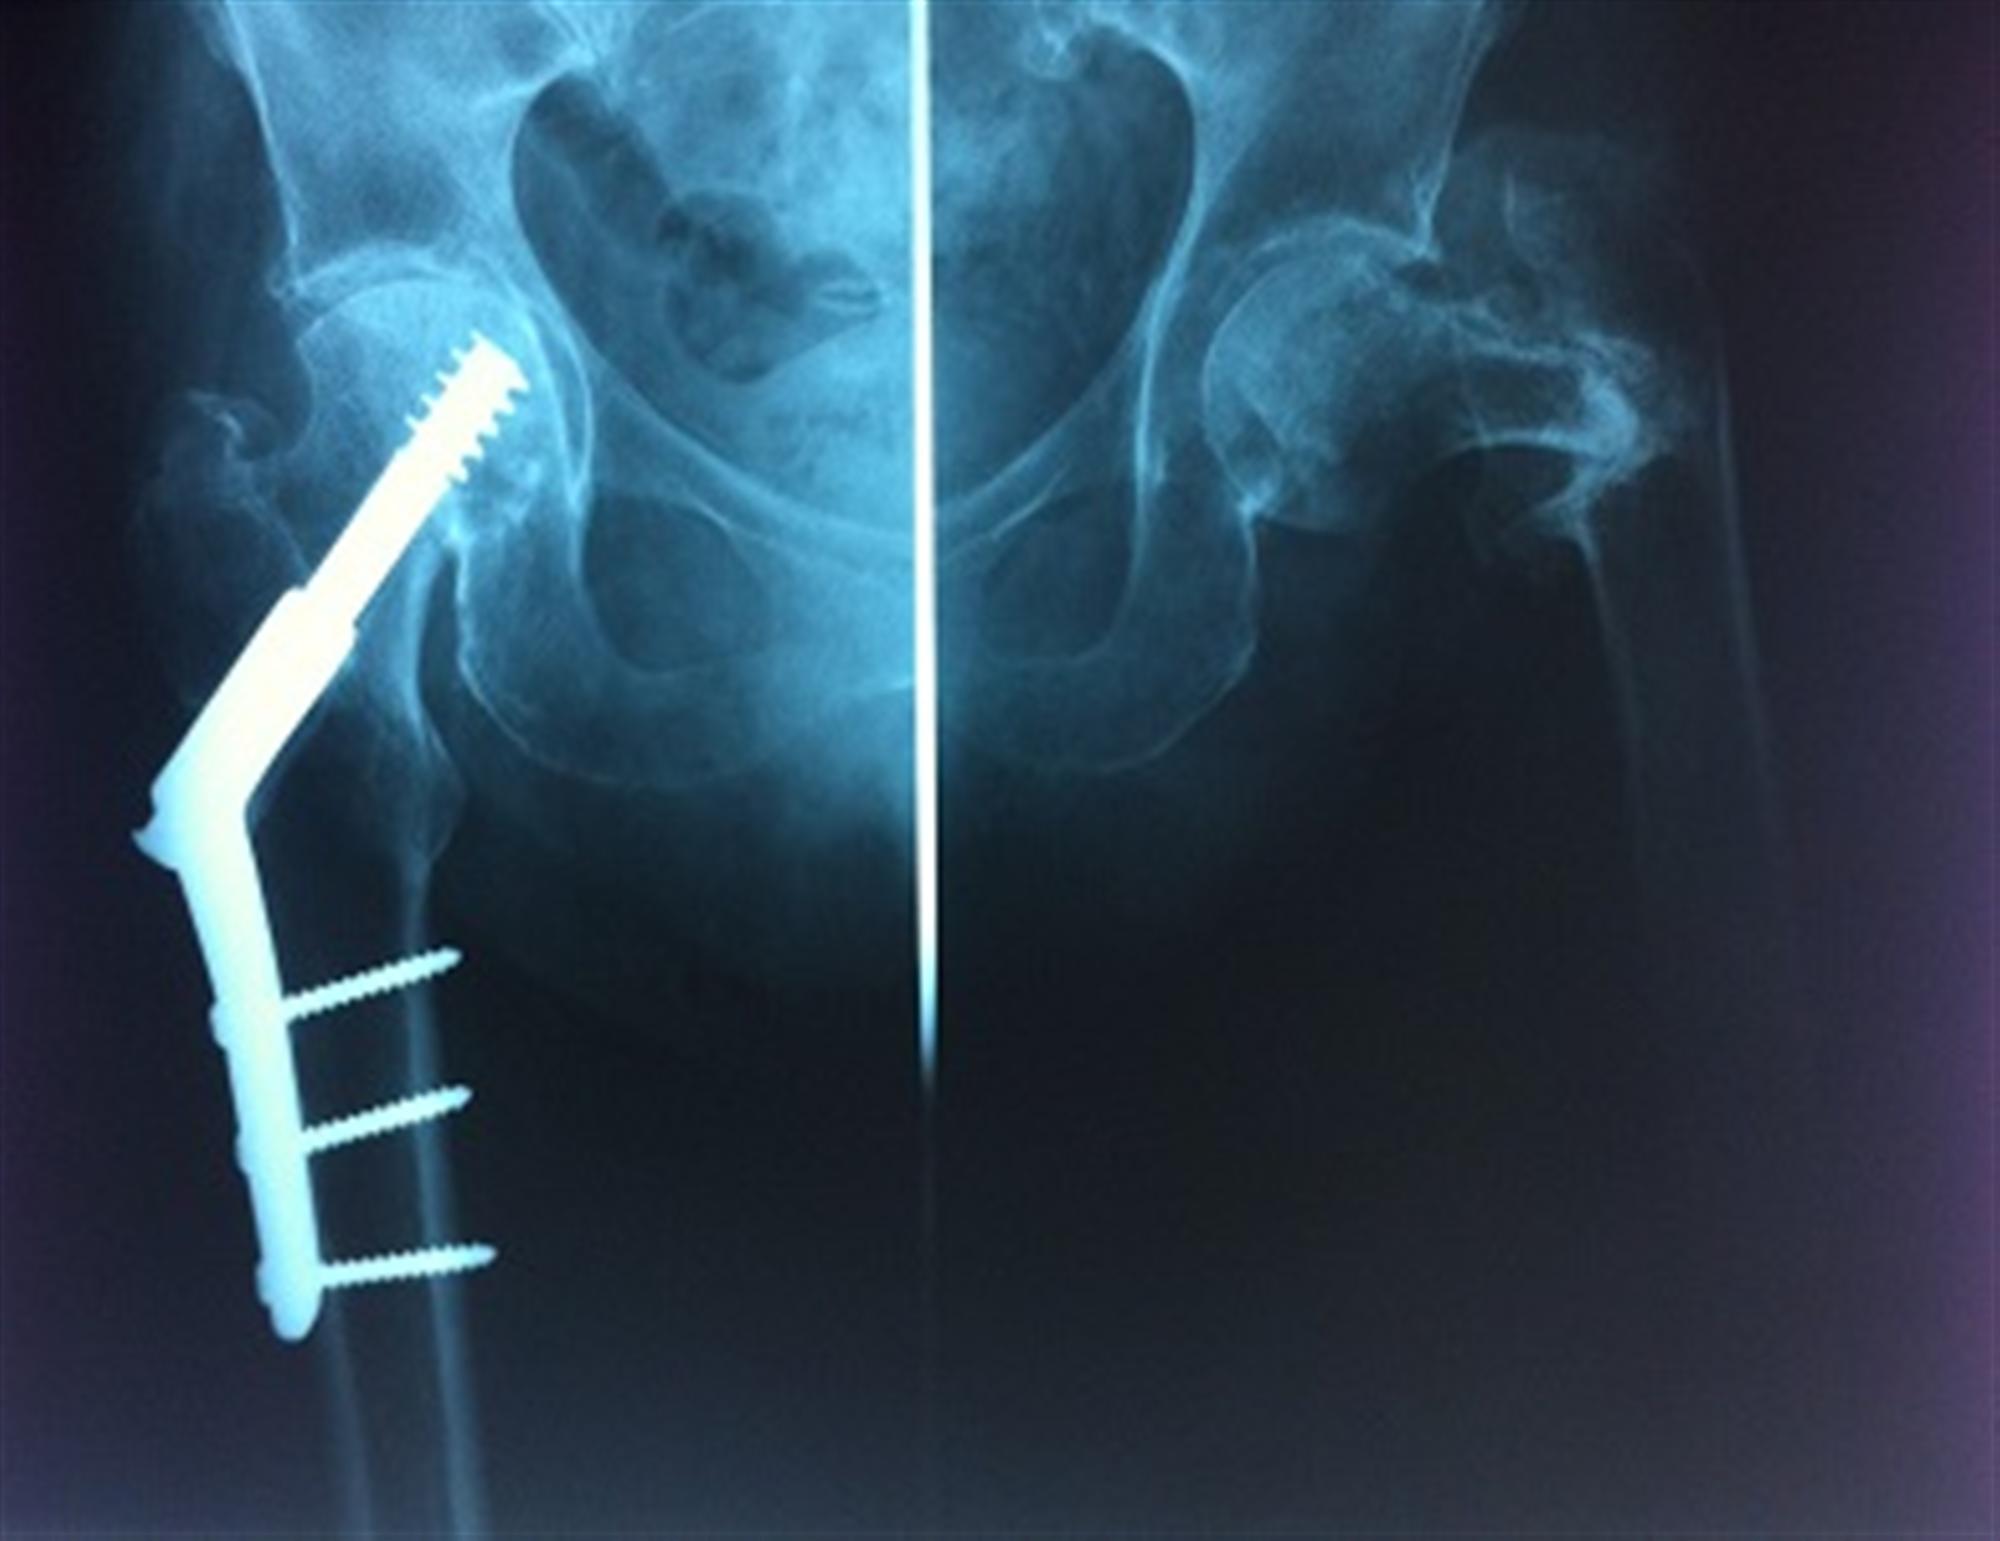

The other cases require surgery to fix the fracture with plates and screws or rods. The garden classification of femoral neck fractures (fnf) dictates treatment via internal fixation or hip replacement, including hemiarthroplasty or total hip arthroplasty. The type of surgery you have will depend on several factors, including:

Fractures that are stable and properly aligned might be fixed with a brace or a cast. What is a fractured neck of femur (hip)? Complications of bipolar hemiarthroplasty include luxation (lower left panel) and protrusion of the acetabulum, her treated by total hip arthroplasty (lower right panel).

Cemented (upper left panel) and press fit technique (upper right panel). A femoral neck fracture is an injury typically sustained by older people. 2 this condition is quite common in the elderly population, specifically females, and hence they are more prone to fractures even due to minor injuries or falls.

The present retrospective study was performed to evaluate the clinical and radiological outcomes of proximal femoral nail antirotation and illustrate its effect on improving the clinical prognosis of basicervical femoral neck fractures. Alternatively, surgery for a fractured neck of femur may involve fixing the broken bone with a screw or a nail, if the bone has a good blood supply. The location of the fracture helps determine the best treatment options.